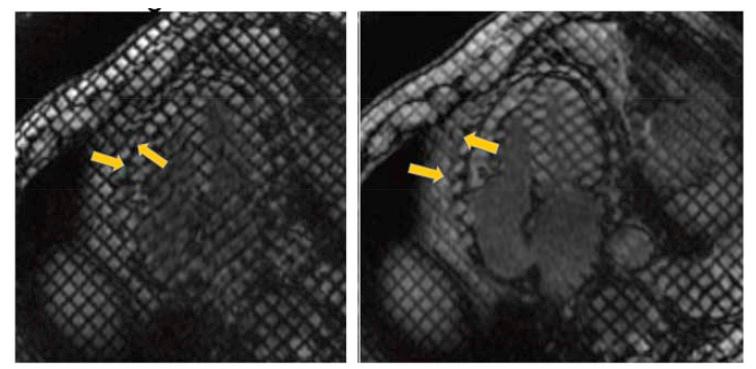

Herein we describe conventional and unique CMR approaches to provide an increased non-invasive understanding of the pericardium in health and disease including a novel method to diagnose constrictive pericarditis via radio-frequency tissue tagging by defining unique visceralparietal adherence patterns easily learned by the cardiologist and radiologist.

在此,我们描述了传统的和独特的CMR方法,以增强对健康和疾病状态下心包的非侵入性理解,包括一种通过射频组织标记诊断缩窄性心包炎的新方法,该方法可定义独特的心外膜-脏层粘连模式,心脏病专家和放射科医生可轻松掌握。

Cardiac magnetic resonance radiofrequency tissue tagging for diagnosis of constrictive pericarditis: A proof of concept study.心脏磁共振射频组织标记术用于缩窄性心包炎的诊断:一项概念验证研究。

J Thorac Cardiovasc Surg. 2016 May;151(5):1348-55. doi: 10.1016/j.jtcvs.2015.12.035. Epub 2015 Dec 21.